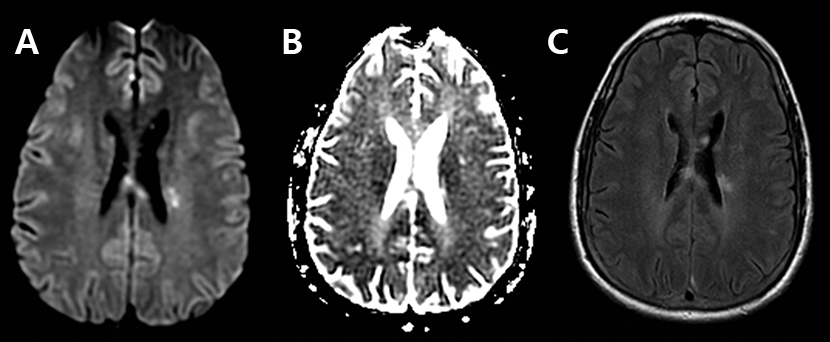

脑卒中影像学鉴别诊断(三):白质异常

830x342 - 147KB - JPEG